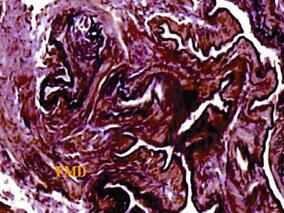

罕见动脉病——纤维肌性结构发育不良两例

1小时条评论肺动脉纤维肌性结构发育不良临床上罕见,且难以诊断。该文系阜外医院病理科阮英茆教授总结发表在中华病理学杂志(1998,27:396-397)上的2例病例报告,尸检证实均为肺动脉纤维肌性结构发育不良,实为难得,特此引用原文。 【临床资料】 例1 患者,女,46岁。因慢...